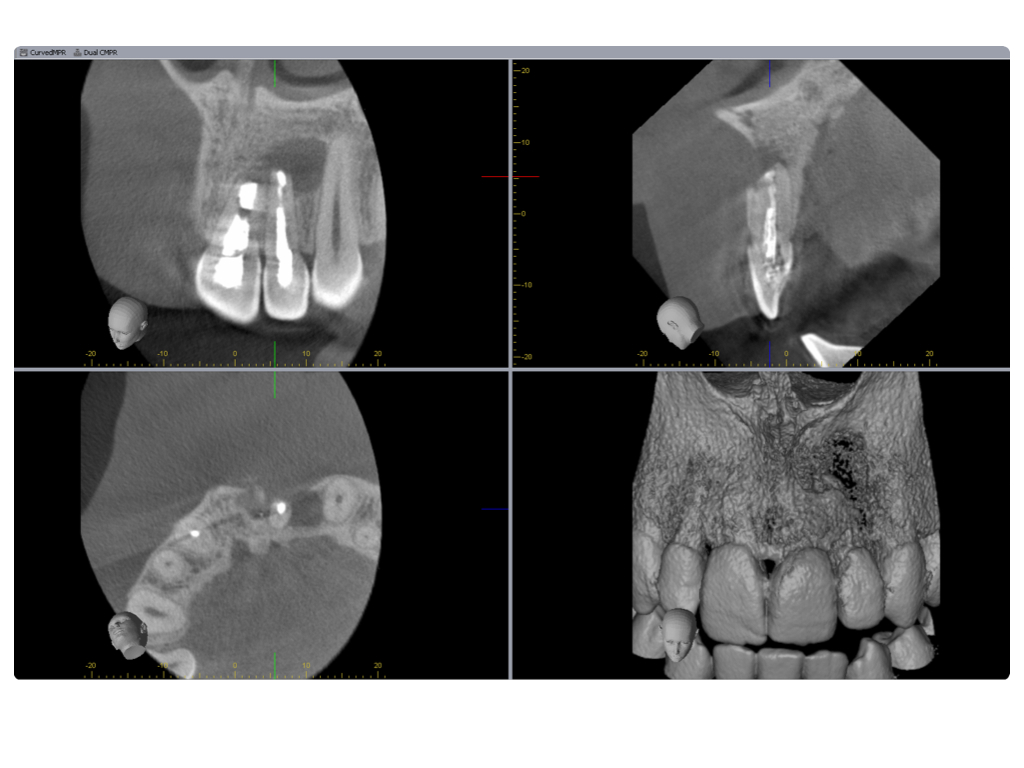

Einbahnstraße WSR (2)

DVT